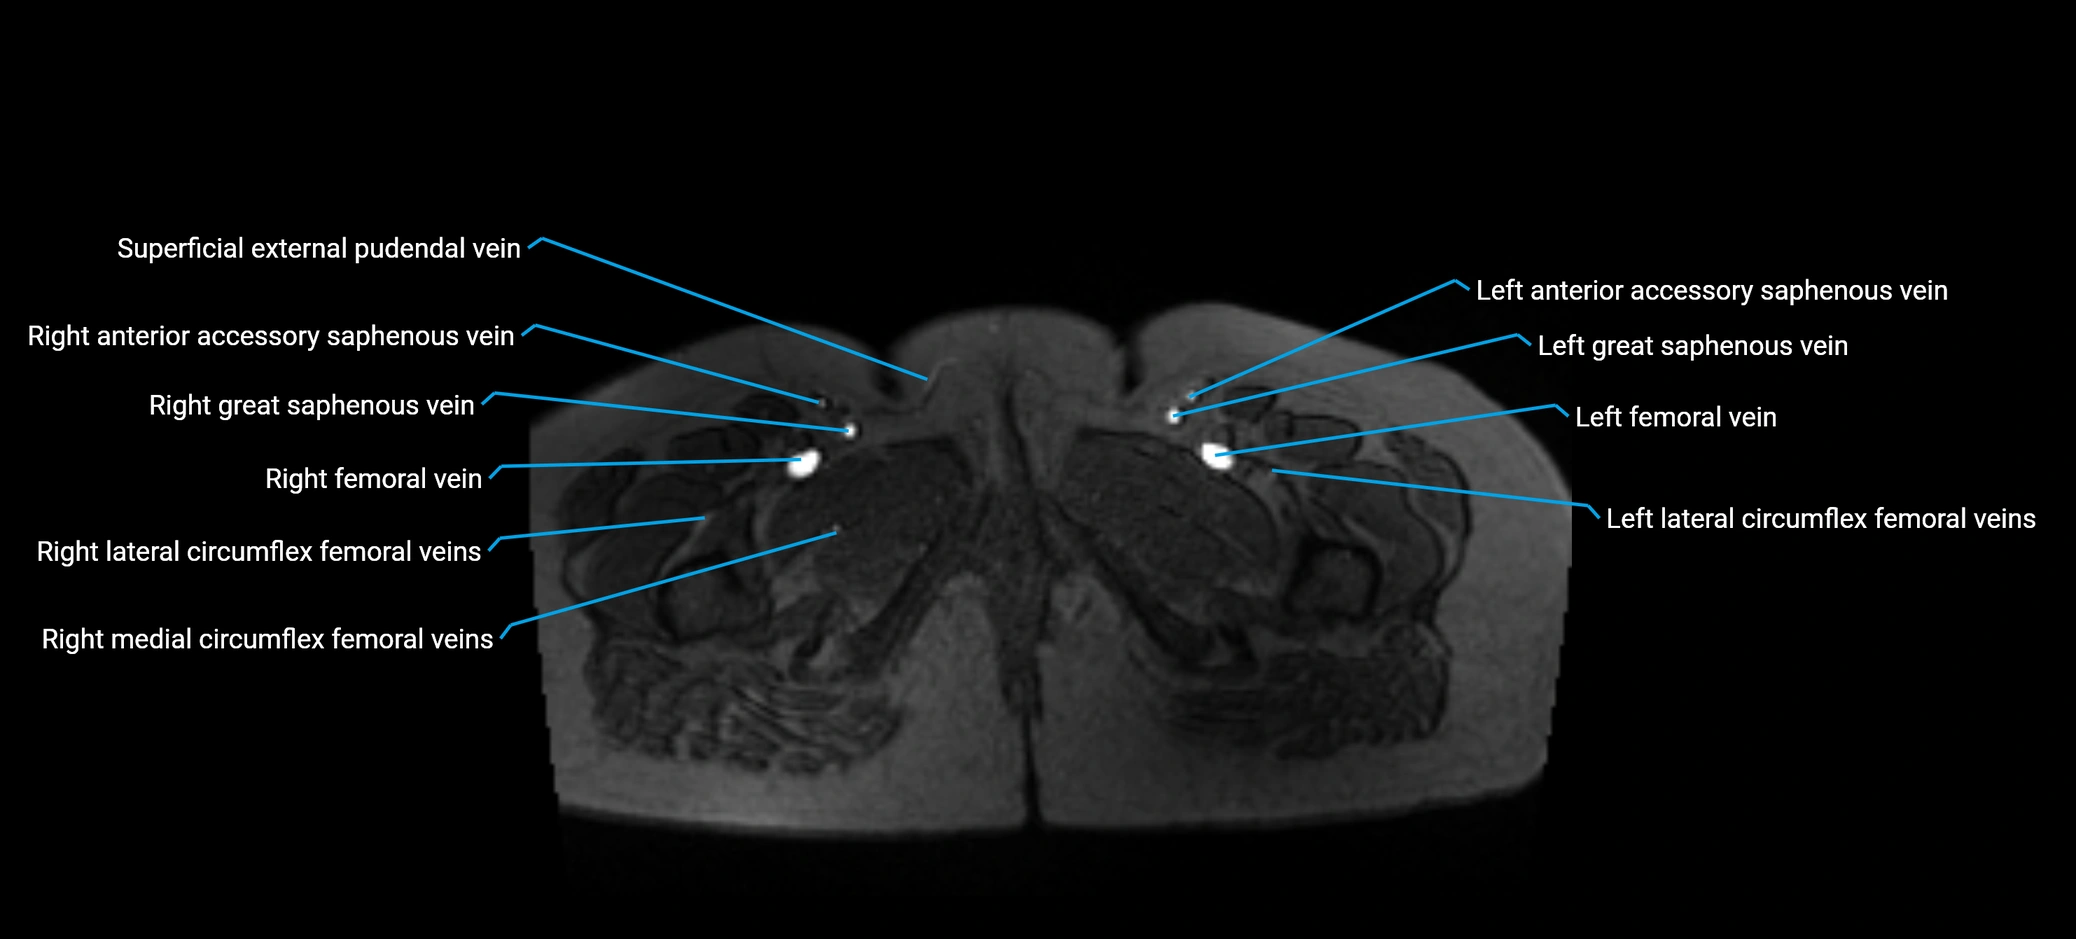

MRI image

image